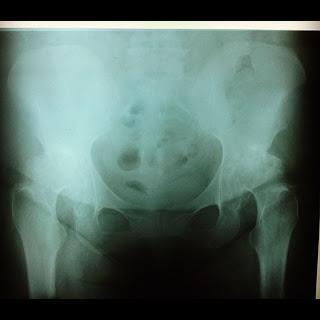

Glucosamina y Condroitin para el dolor articular de la artrosis

Glucosamina y condroitin para mejorar el dolor articular en la artrosis.He realizado una revisión sistemática de todos los trabajos científicos disponibles sobre el uso de la combinación de Glusomina y Condroitin, la idea es objetivar los resultados a favor y en contra del uso de la medicación.